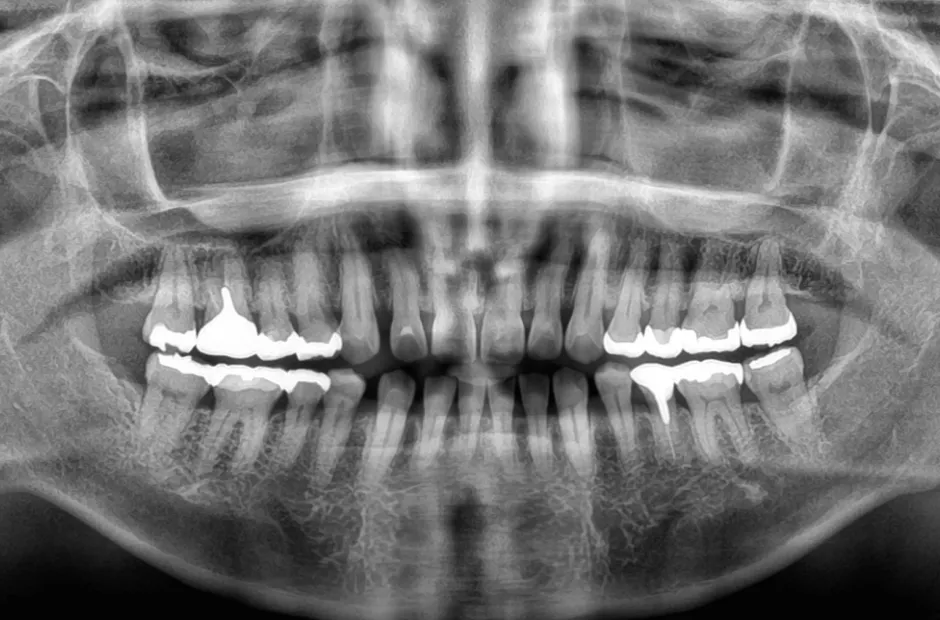

叢生

| 診断名・主訴 | 叢生 |

|---|---|

| 年齢・性別 | 43歳・女性 |

| 治療期間・回数 | 2年7か月 27回 |

| 治療に用いた主な装置 | 舌側矯正 |

| 抜歯部位 | 両顎4,4 |

| 治療費 | 100万円(税抜) |

| リスク・副作用 | 装置による違和感・疼痛・歯肉退縮・歯根吸収・虫歯のリスクなど |

治療前